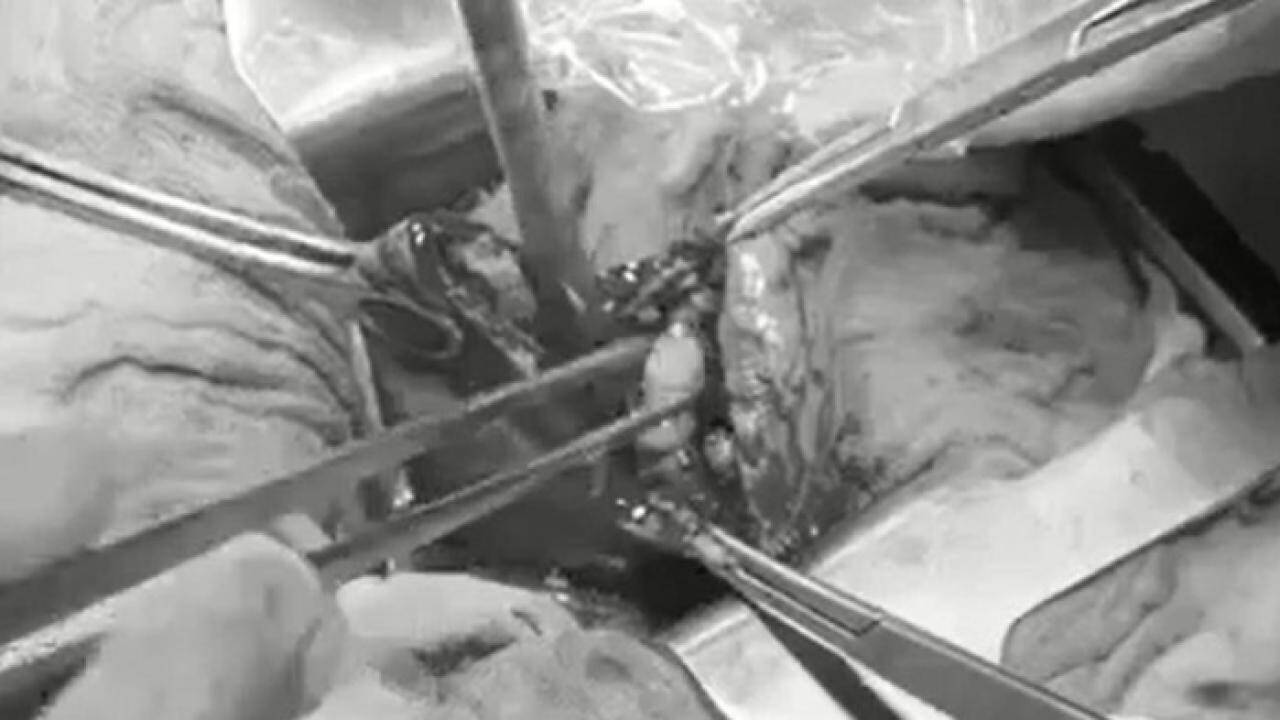

Sau khi được ê-kíp bác sỹ nội soi lấy sỏi ống mật thành công, hiện sức khỏe của bệnh nhân nhi tốt, hết tắc mật và dự kiến có thể xuất viện trong một vài ngày tới. Ảnh: Nhật Tân

Ca phẫu thuật được thực hiện với ê-kíp y bác sĩ do Ths.BS. Nguyễn Văn Duy và BS. Trần Hiếu thực hiện và sau 30 phút tiến hành thủ thuật, ê-kíp đã lấy sỏi thành công.